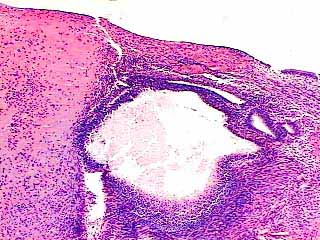

fig. 1

Figura 1. Superficie mucosa endocervical que muestra un nódulo hialinizado. H&E 40x